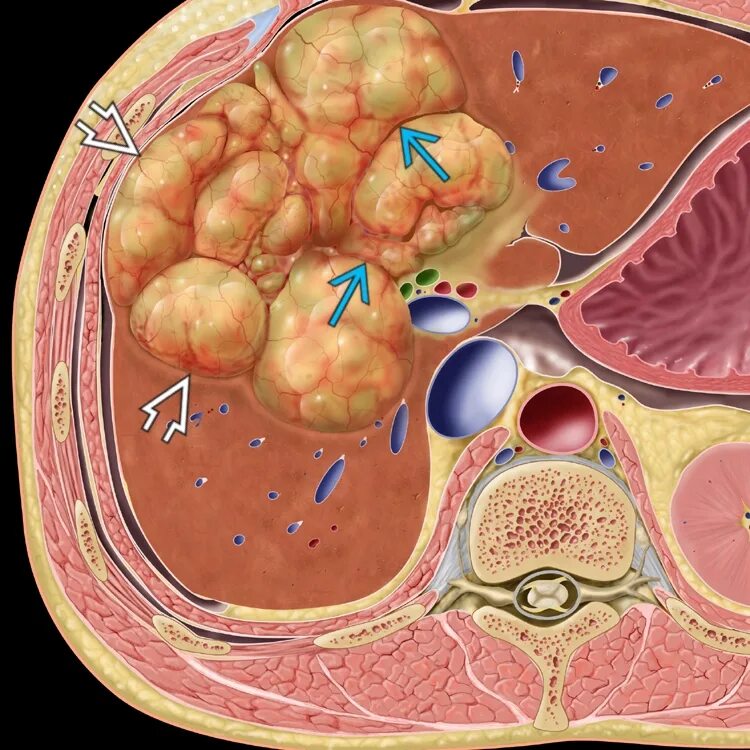

Advanced tumor